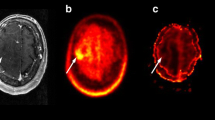

Perfusion MRI

The rCBVmax ratios in the PET hotspot and the rCBV ratios in the large tumor ROI for each case (n = 24) are shown in Table 1. The mean rCBVmax in PET hotspot regions for the whole sample was 3.19 ± 1.66 (range 0.92–8.27) (Fig. 1a). The mean rCBV in the large tumor ROI was 0.99 ± 0.77 (range 0.28–4.24), which was significantly lower (P = 0.0001). Regions with rCBVmax corresponded to hotspot regions on PET in all cases. The correlation between rCBVmax ratios in the hotspot region and HS/cortex ratios is shown in Fig. 1b (Spearman’s r = 0.19, P = 0.38). There was a significant difference in mean rCBVmax between gliomas grade II and gliomas grade III (P = 0.04), but not between enhancing and non-enhancing lesions (P = 0.34).

In the present study, we investigated 24 patients with suspected LGG by morphological MRI, physiological MRI and MET PET prior to surgery. Our aim was to define the correlation between MET uptake and perfusion and diffusion abnormalities in these tumors at the time point of radiological diagnosis. We found that regions with rCBVmax corresponded with hotspot regions on PET in all tumors. However, in spite of a consistent topographical overlap between hotspot on MET PET and areas with maximum tumor perfusion, there was no significant positive correlation between rCBVmax and highest MET uptake. Our results are in contrast to a previous study, reporting a positive correlation between rCBVmax and maximum MET uptake and indicating a close link between amino acid transport in the tumor and vascularity [31]. This discrepancy may be partly due to the different study populations and methodologies, but also to the general difficulties of measuring subtle differences in regional perfusion in non-enhancing infiltrating tumors [32]. It is difficult to select a ROI with high intra- and inter-observer reproducibility in LGG, since perfusion images are noisy compared to both morphological images and MET PET scans. Susceptibility artifacts with signal loss and adjacent signal increase, simulating perfusion increase, may also disturb perfusion images. In addition, high perfusion values in vessels and adjacent cortex may be difficult to differentiate from increased tumor perfusion. Therefore, pMRI alone appears to be unsuited to replace MET PET in providing reliable baseline data on tumor vascularity. This is further illustrated by our perfusion measurements calculated within a large tumor area and without prior knowledge of MET PET, which were significantly lower than the co-registered PET/MRI measurements. The present study shows that the co-registered measurement of rCBVmax and MET uptake is a reliable way to define perfusion abnormalities in LGG (illustrated in Fig. 3).

Patient 8. Preoperative MET PET and MRI of a right-sided frontal oligodendroglioma grade II in a 31-year-old female. a MET PET shows the hotspot region of the tumor. b T2-weighted FLAIR MRI shows a high signal intensity tumor. c T1-weighted contrast-enhanced MRI shows minimal contrast enhancement in the tumor area. d DSC perfusion MRI with rCBV color map shows high perfusion in the tumor area. e DSC perfusion MRI with rCBV grey-scale map shows high perfusion in the region corresponding to the PET hotspot. The ROIs in the tumor and in the contralateral normal appearing white matter are marked. f dMRI where the MDmin value in the region corresponding to the PET hotspot is lower than MD in the medial portion of the tumor (but minimally increased compared to normal appearing contralateral white matter)